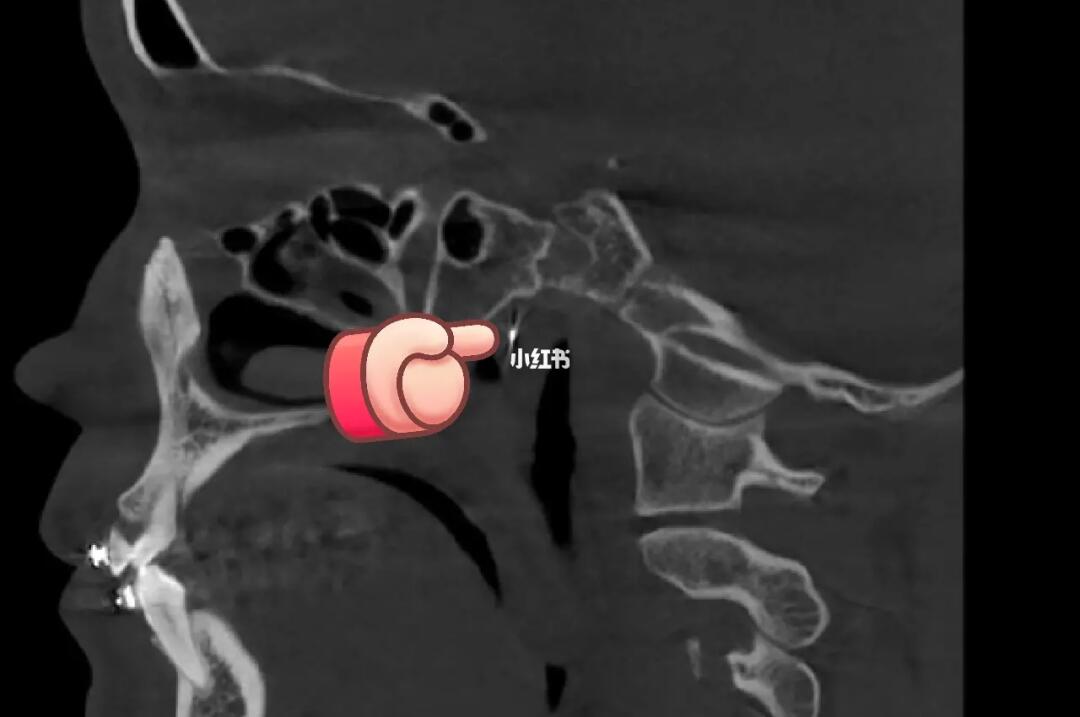

[惊恐R]通过拍片发现,上颌牙的正畸钢丝越过翼静脉丛都快插进颅内了[惊恐R]都靠近脑膜中动脉了,这要是再深一点或者偏一些[惊恐R]刺破了血管,后果不堪设想!